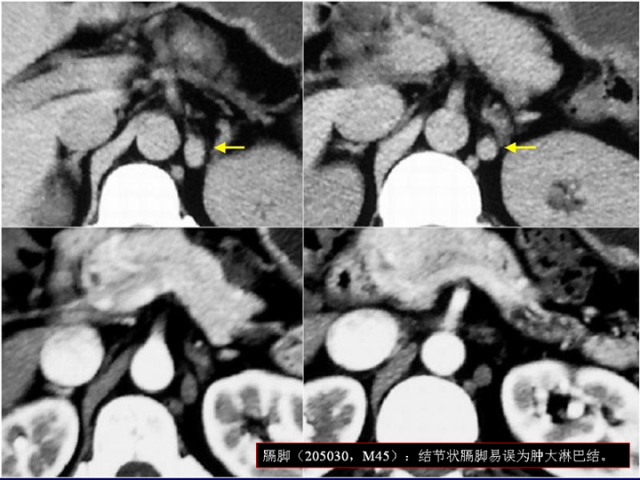

膈肌角解剖及常见变异

作者:王俭 上海长征医院